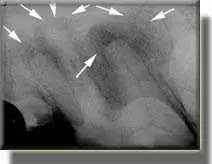

Another reason for considering root canal therapy is when we find radiographic evidence of infection inside the tooth. A tooth can become infected inside from a very small chip or fracture. The infection hides inside the tooth and then trickles out the ends of the roots, damaging the surrounding bone.

This bone damage can sometimes be seen on a dental X-ray. When a tooth is infected inside it can either be extracted or treated with root canal therapy. Root canal therapy on an infected tooth can almost always be performed, but occasionally there is too much damage to the roots from long-term infection to allow treatment.

Large chewing tooth on the left upper side, showing damaged areas of bone around the ends of the roots (arrows), caused by infection inside the tooth leaking out the ends of the roots.